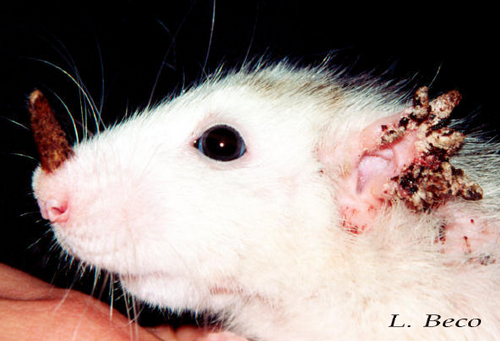

in the red foxSummary There are several different types of mange each caused by a different species of mite but sarcoptic mange most commonly affects foxes Sarcoptic mange is a skin disease caused by the small 2 to 4 mm or less than one quarter of an inch parasitic mite Sarcoptes scabiei several thousand of which may burrow into a single square centimetre of skin Notoedric Mange In Humans britishhamsterassociation uk dermatitis htmDermatitis by Liz Johnson If we suspect dermatitis in a hamster we should first exclude the possibility that what we see is simply a normal scent gland as seen over the best cat art Cat CareCat hair loss is not that uncommon and can be caused by many different ailments and problems Your veterinarian is the best person from whom to obtain advice diagnosis and treatment

catdandruffclinic cat mange feline scabies all you need to Cat Mange is a skin disease caused by various tiny mite species Some of the causative mange mites are normal residents of your cat s skin and hair follicles while others are considered parasites Notoedric Mange In Humans best cat art Cat CareCat hair loss is not that uncommon and can be caused by many different ailments and problems Your veterinarian is the best person from whom to obtain advice diagnosis and treatment vetstreet why does my cat scratch her earsEar scratching is one of the more common reasons cats see veterinarians When the head starts shaking and claws start digging it s a safe bet that a cat has itchy ears But the cause is not always clear

Animal Dermatology Clinics - Newsletter, image source: www.icb.usp.br

Notoedric mange - Parasites - parasitic skin conditions, image source: www.animaldermatology.com

Notoedric mange - Parasites - parasitic skin conditions, image source: ebookcvm.contentoro.net